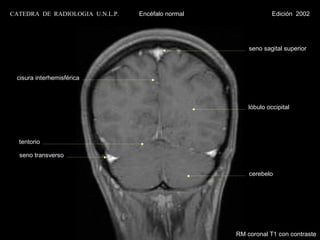

seno sagital superior

cisura interhemisférica

lóbulo occipital

tentorio

seno transverso

cerebelo

RM coronal T1 con contraste